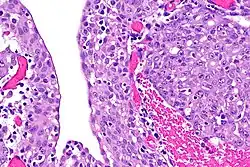

| Renal medullary carcinoma (right of image), reactive urothelium and sickled red blood cells. H&E stain. | |

The finding that virtually all people affected by renal medullary carcinoma carry at least one copy of the HbS mutation suggests that sickle cell trait somehow predisposes to this type of cancer.[5] The precise mechanism is unknown, but red blood cells with a sickle cell configuration have been identified in pathology specimens.[2]